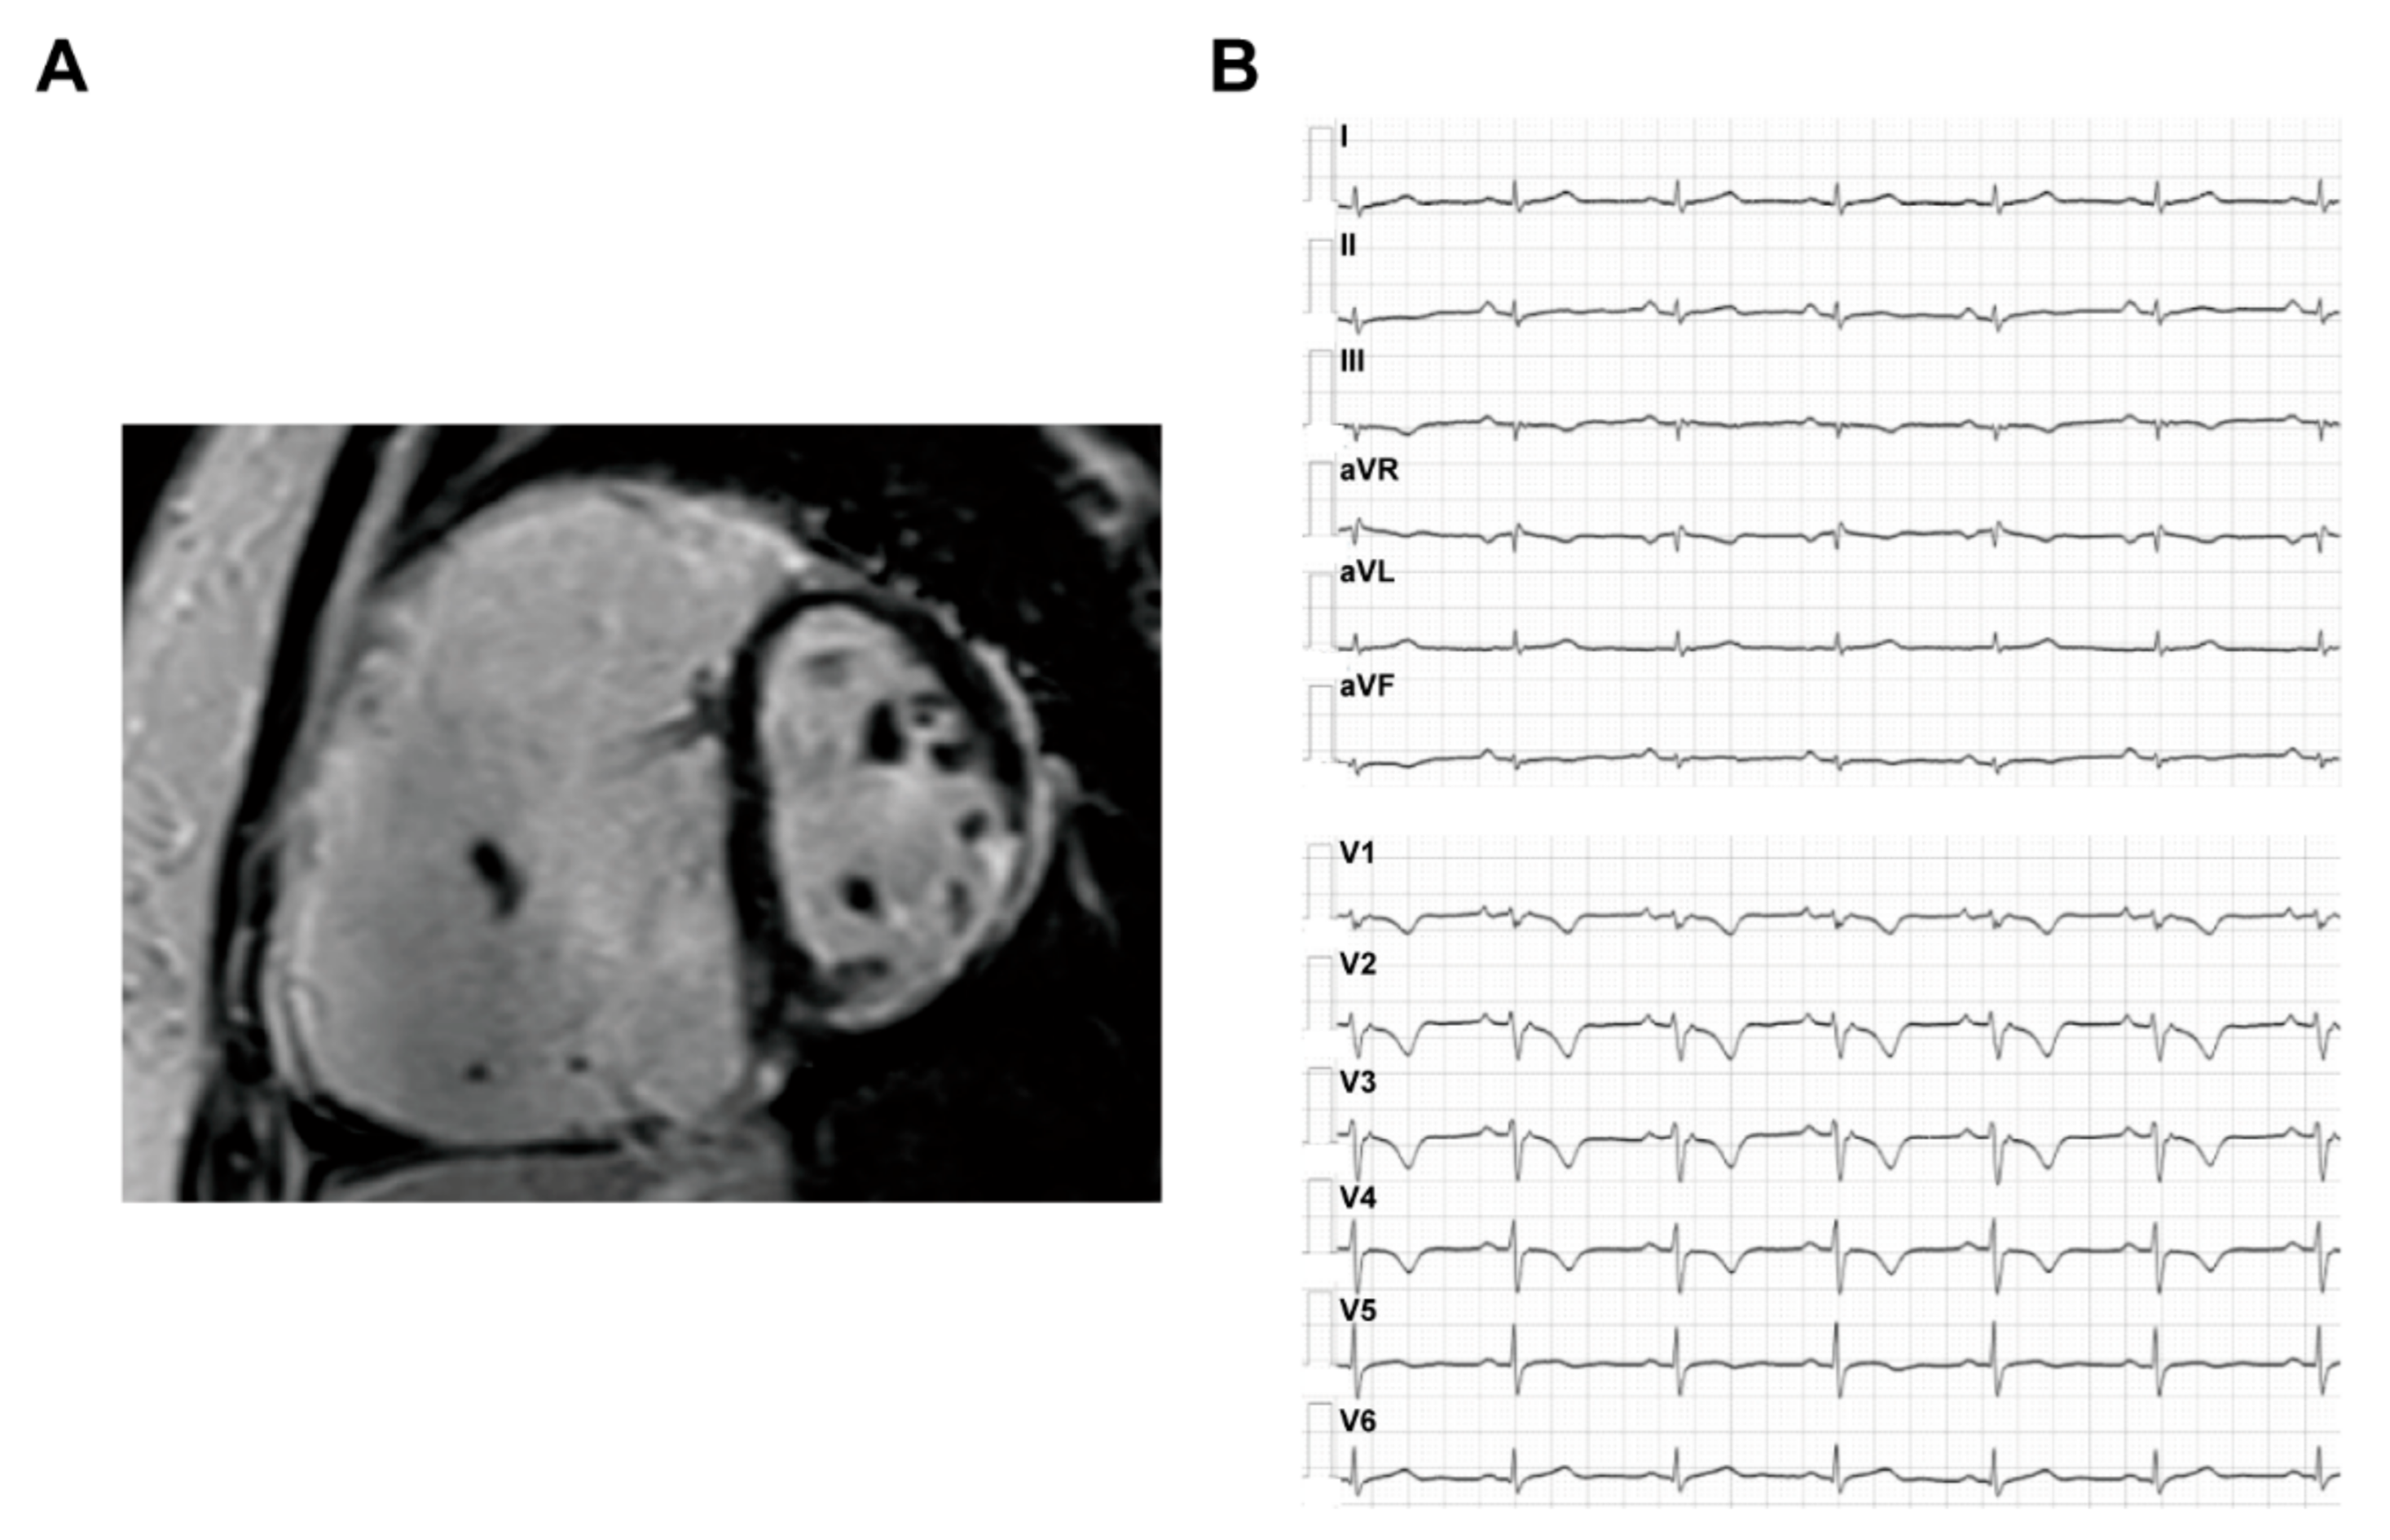

3.1.2. Imaging and ECG Phenotype